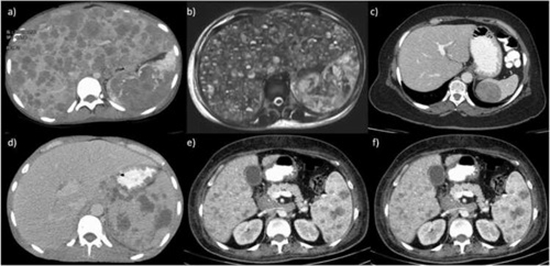

Diagnostic performance of different imaging modalities for splenic malignancies: A comparative meta analysis

Background and objectives: The spleen hosts both benign and malignant lesions. Despite multiple imaging modalities, the distinction between these lesions poses a diagnostic challenge, marked by varying diagnostic accuracy levels across methods. In this study, we aimed to evaluate and compare the diagnostic performance of various imaging techniques for detecting malignant splenic lesions.

Results: Our study included 28 studies (pooled sample size: 2358), primarily using retrospective designs with histopathology as the reference standard. PET scan demonstrated the highest diagnostic accuracy (AUC: 92 %), demonstrating a sensitivity of 93 % (95 % CI: 80.4 % - 97.7 %) and a specificity of 82.8 % (95 % CI: 71.1 % - 90.4 %). Contrast-enhanced ultrasound (CEUS), Contrast-enhanced CT scan, and contrast-enhanced MRI also showed impressive performance with AUCs of 91.4 %, 90.9 %, and 85.3 %, respectively. Differences among these modalities were not statistically significant, but they outperformed non-contrast-enhanced methods. PET and CEUS exhibited higher specificity for lymphoma cases compared to studies including other malignancies.

Conclusion and clinical implications: Overall, PET emerges as the best modality for splenic malignancies, and CEUS and CE-MRI show promise as potential alternatives, notably due to their reduced radiation exposure. Further research is essential for precise malignancy differentiation.